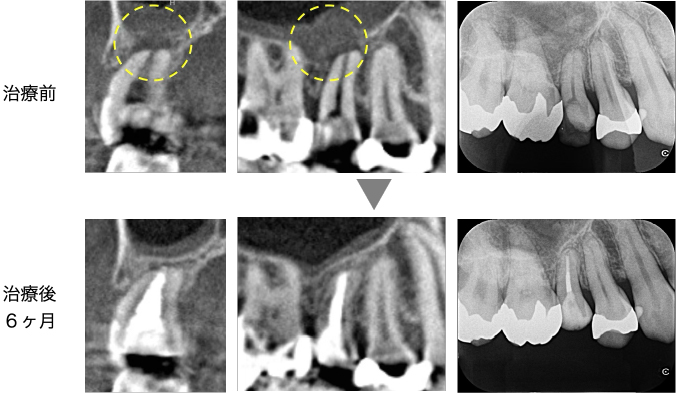

根管治療後6ヶ月のCT画像にて、元々失われていた骨が完全に再生していることが確認できました。

上顎洞の骨も回復し、上顎洞炎も消失し、良好な経過を辿っています。

術後、ひびく感じが強くあるのとのことでしたが、6ヶ月経過時点では軽減し、レントゲン・CTでも骨の回復が認められました。